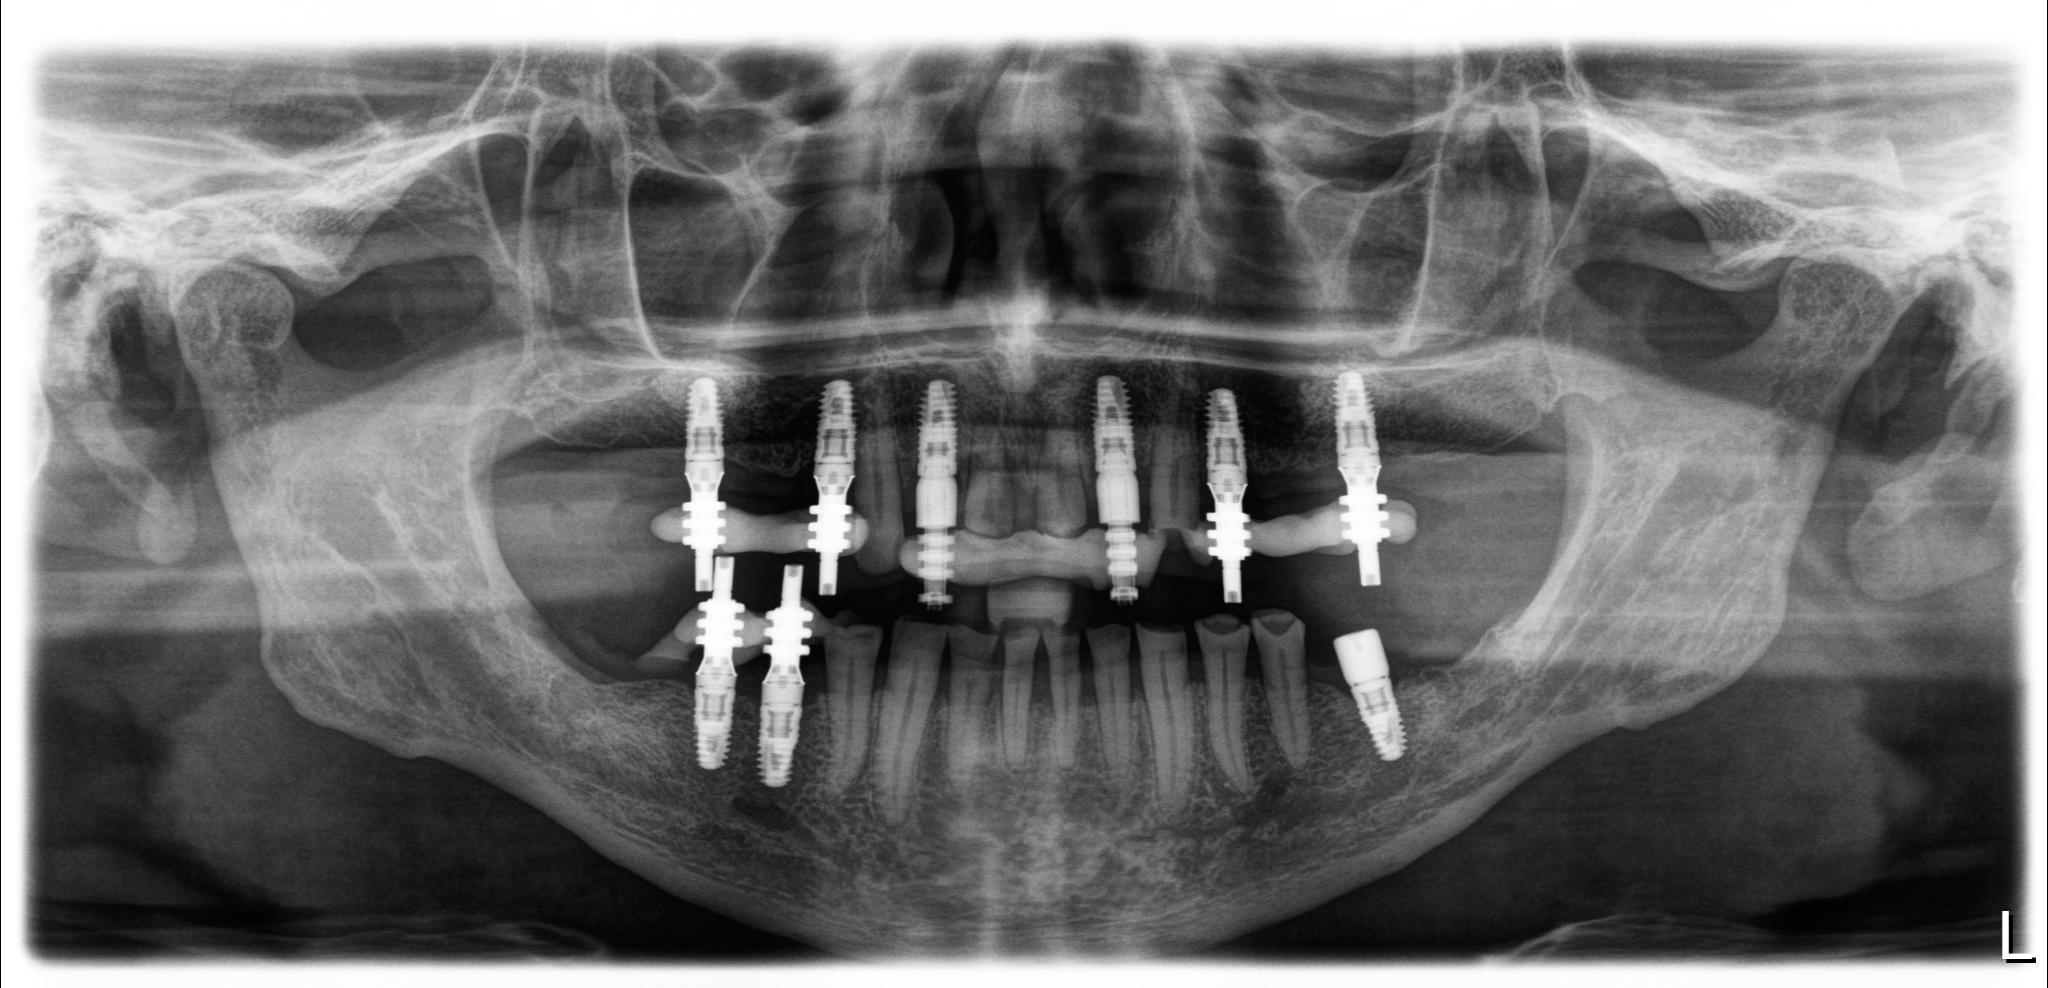

Я подготовился к приему заранее, посмотрел компьютерную томографию, которую он мне прислал.

По снимку видно, что необходим комплексных подход к проблеме, который будет включать в себя мою работу, как хирурга, так и смежных специалистов. Гигиениста, ортопеда и терапевта.

Дабы не перегружать вас обилием одинаковых картинок, я оставлю один рентгеновский снимок, но отмечу, что установка имплантатов на верхней и нижней челюсти проводилась с разницей в 10 дней.

На верхней челюсти было дополнительно удалено два боковых резца с одномоментной установкой имплантатов, так же они были установлены в области четверок и шестых зубов. Дополнительно было проведено наращивание костной ткани - двусторонний синус - лифтинг. О том, что это такое, можно почитать ТУТ и ТУТ.